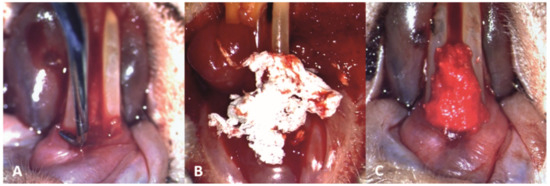

3.2. Treatment

The mechanical debridement was performed gently to the subjects in groups T1 and T2, using the modified Gracey curette, in order not to cause damage to the inflamed periodontal tissues (Figure 4A). Subsequently, in subjects from the T1 group, the novel biomaterial was applied in the periodontal pockets on the buccal, distal and mesial surfaces of the teeth, and interdentally between the two lower incisors (Figure 4B,C).

Figure 4. Clinical aspect of the periodontal treatment (10× magnification): (A) mechanical debridement of the lower incisors; (B) application of the novel biomaterial obtained through electrospinning; (C) final aspect of the material applied at a sulcular level and interdentally between the two lower incisors, saturated with blood and promoting local hemostasis.